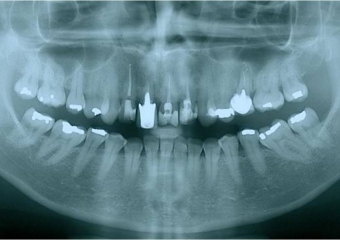

Raio X final